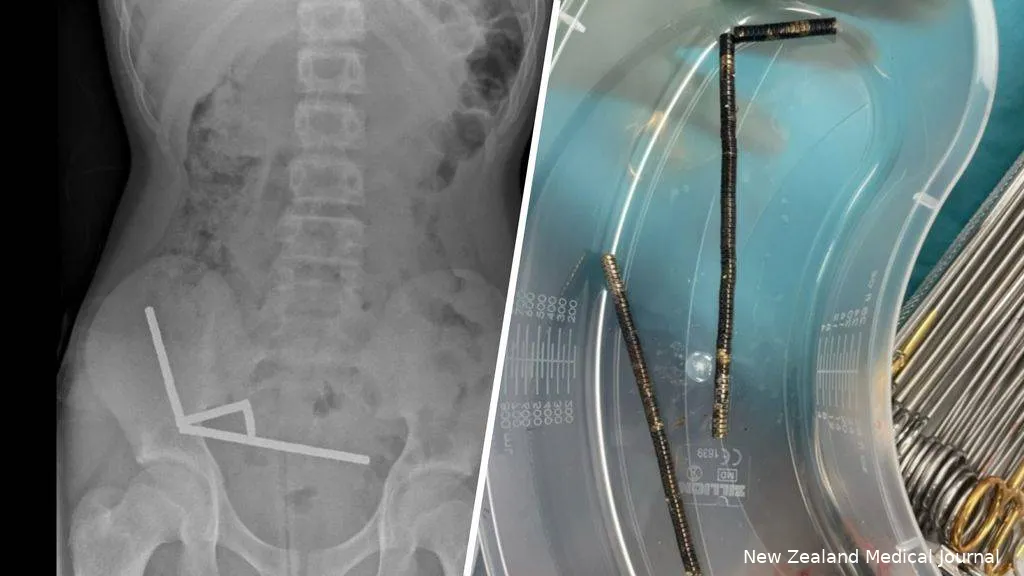

Magneten hebben een natuurlijke aantrekkingskracht, maar om ze nou in groten getale naar binnen te werken... Een 13-jarige jongen uit Nieuw-Zeeland heeft een zware operatie moeten ondergaan nadat hij tussen de tachtig en honderd kleine, krachtige magneten had ingeslikt. De magneetjes trokken elkaar in zijn buik aan, waardoor delen van zijn darmen afstierven en moesten worden verwijderd.

De jongen werd na vier dagen met hevige buikpijn opgenomen in het ziekenhuis. Daar biechtte hij op dat hij de magneten een week eerder had doorgeslikt, meldt het New Zealand Medical Journal (NZMJ). Op röntgenfoto’s zagen artsen dat de bolletjes zich hadden samengeklonterd. Een deel van zijn darmen was daardoor onherstelbaar beschadigd.